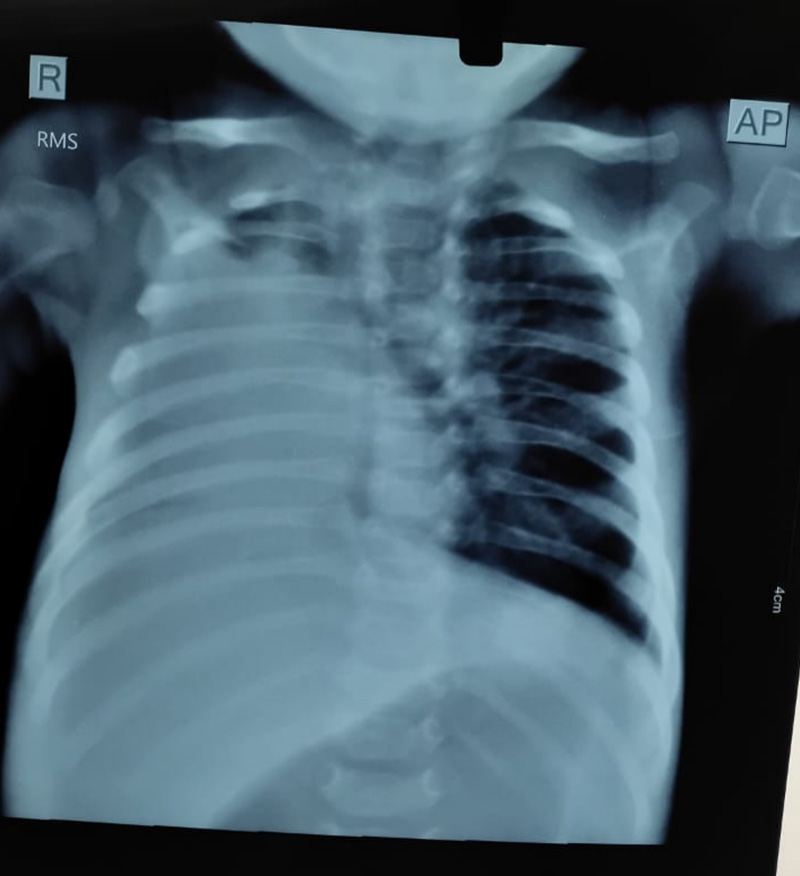

• Chest X-rays post-bronchoscopy showed clear re-expansion of the affected lung area

• The infant was gradually weaned off oxygen and is currently stable and recovering well